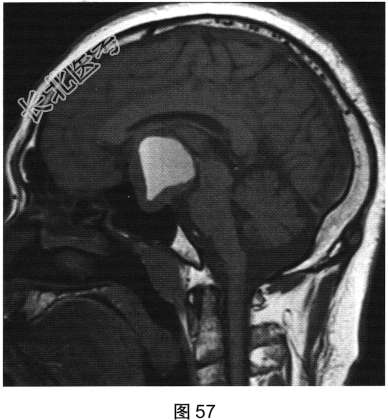

- 多项选择题2.[提示]患者行垂体MRI检查,见图55~图59。患者MRI检查可见哪些阳性影像学表现( )

A、矢状位增强扫描显示垂体及垂体柄显示不清

B、冠状位T1WI上呈等高信号

C、矢状位T1WI上视交叉抬高

D、冠状位T2WI上呈等高信号

E、矢状位T1WI上垂体显示不清

F、冠状位T1WI上可见钙化信号影

G、冠状位增强扫描显示实性部分明显均匀强化

H、MRI示鞍区囊实性占位性病变

I、冠状位增强扫描显示双侧海绵窦受侵